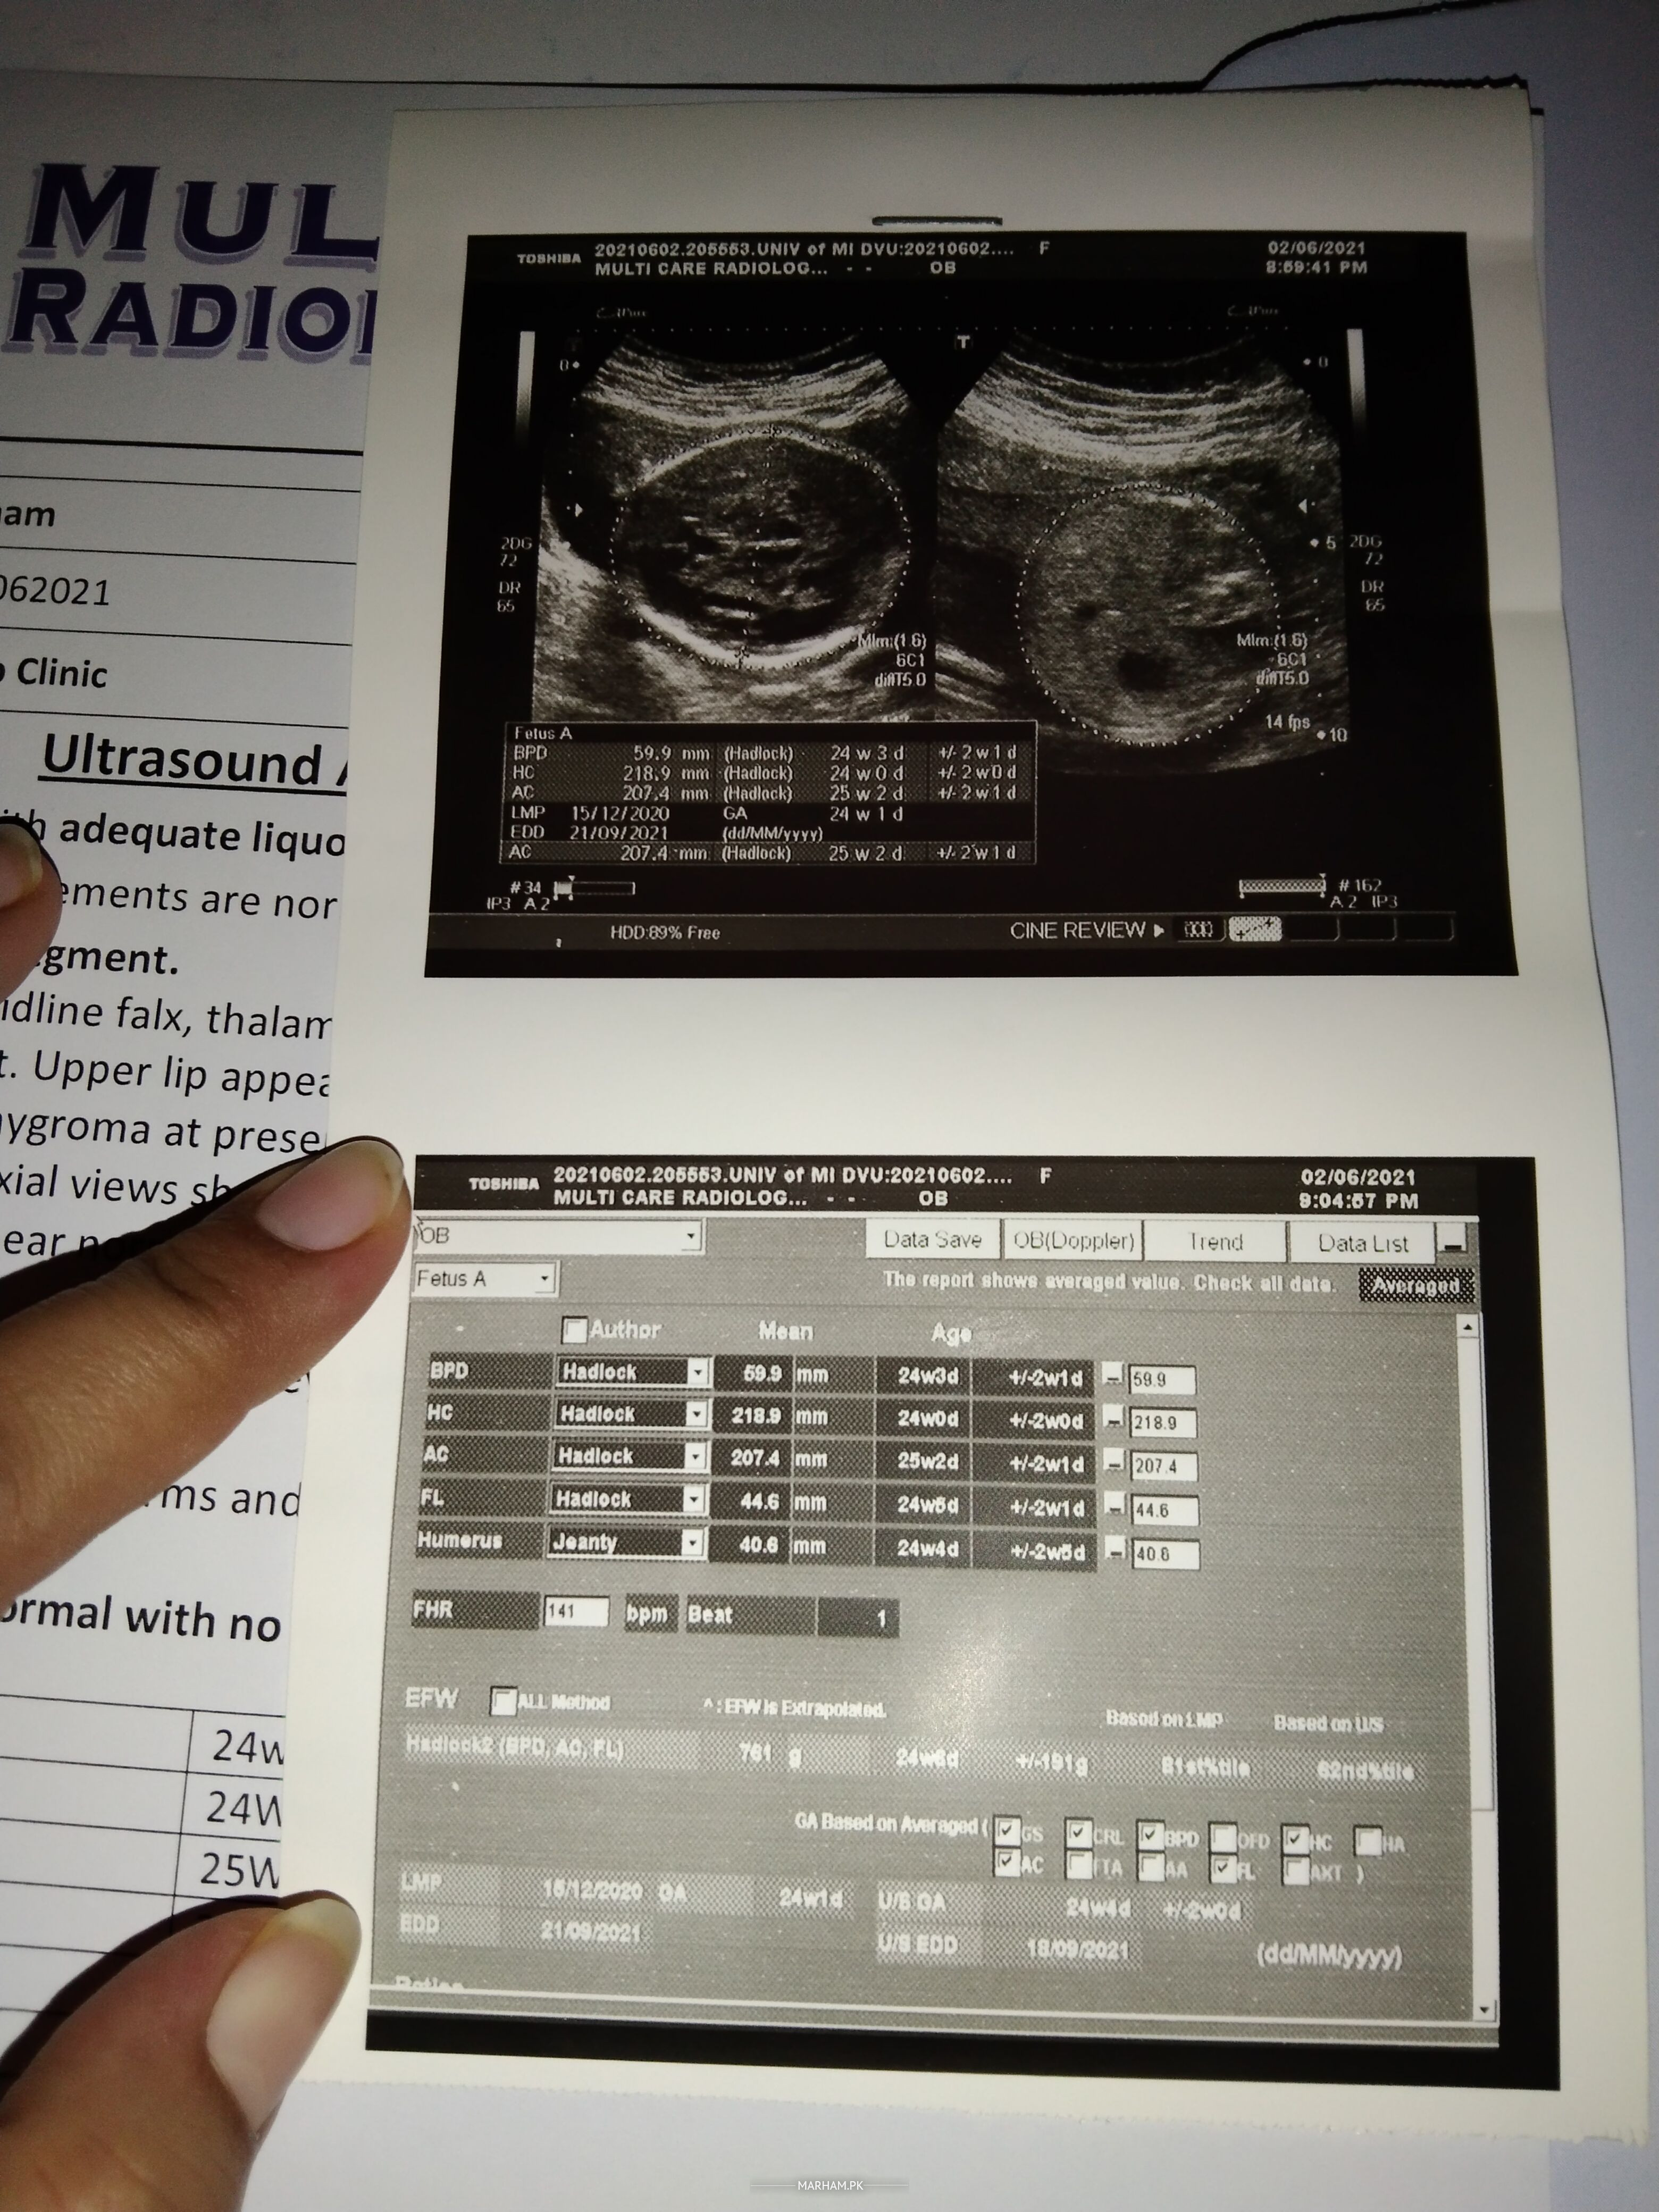

Ye meri ultrasound report ha

Ye pic b